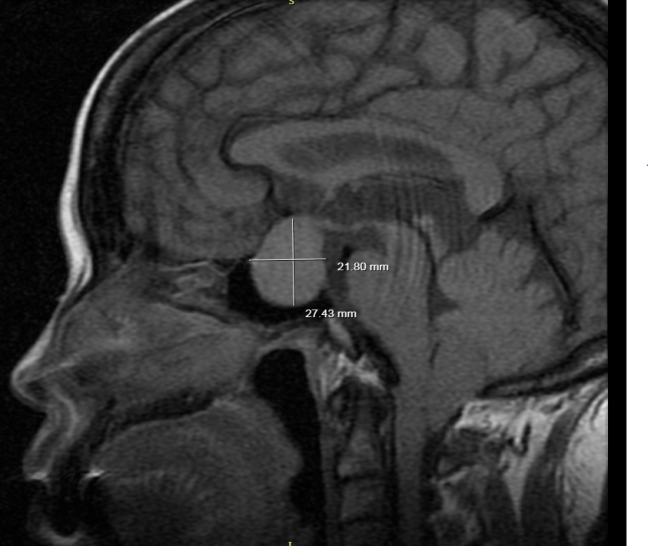

患者女性,50岁,因“头昏、视物不清2年,加重10+天”入院。入院完善头部X线计算机体层(CT)平扫:蝶鞍扩大并其内占位灶,建议MRI平扫+动态增强检查。双侧上颌窦及左侧筛窦炎。进一步完善垂体MRI平扫+增强:蝶鞍区扩大,垂体窝内见斑片状等T1、等稍短T2信号,形态欠规则,冠状位示病灶呈“雪人征”,测量其大小约26mm×27mm,垂体柄显示不清晰,视交叉受压上抬移位,鞍底塌陷,增强扫描可见病灶轻度强化,强化尚均匀。考虑垂体大腺瘤,建议结合病理检查。

术前头颅核磁